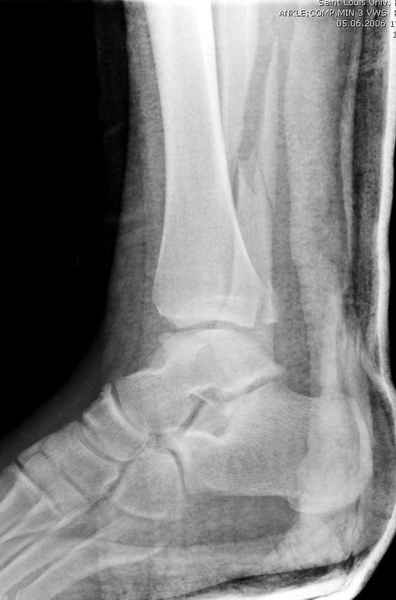

Конечно, компьютерный томограф более информативный метод, но с помощью недорогого обычного стандартного в нейтральном положении стопы: прямого, бокового и косой (ankle mortise) ренгенологического метода можно получить полную информацию о повреждении голеностопного сустава, а сравнительный снимок с другой стороны подтвердить наличие повреждения.

При реконструкции голеностопа, о важности восстановления длины малоберцовой для профилактики пост травматического артроза разбирали в предыдущих дискуссиях. Нарушенную биомеханику голеностопа без восстановления длины малоберцовой, не восстановить только швом медиальной связки.

Расширенная медиальная щель более чем на 4 мм и укорочение малоберцовой более чем 2 мм, а перелом заднего края большеберцовой смещения более 2мм с вовлечением 30% поверхности сустава, считается отходом от нормы голеностопного сустава, и подлежит к оперативному вмещательству.

Здесь похожий случай трехнедельной давности, перелом почти сросся и была укорочена малоберцовая, на операции длину малоберцовой смогли восстановить только после того, когда проксимальнее пластины ввели шуруп и использовали его как толкатель, с помощбю дистракционого инструмента (lamina spreader).